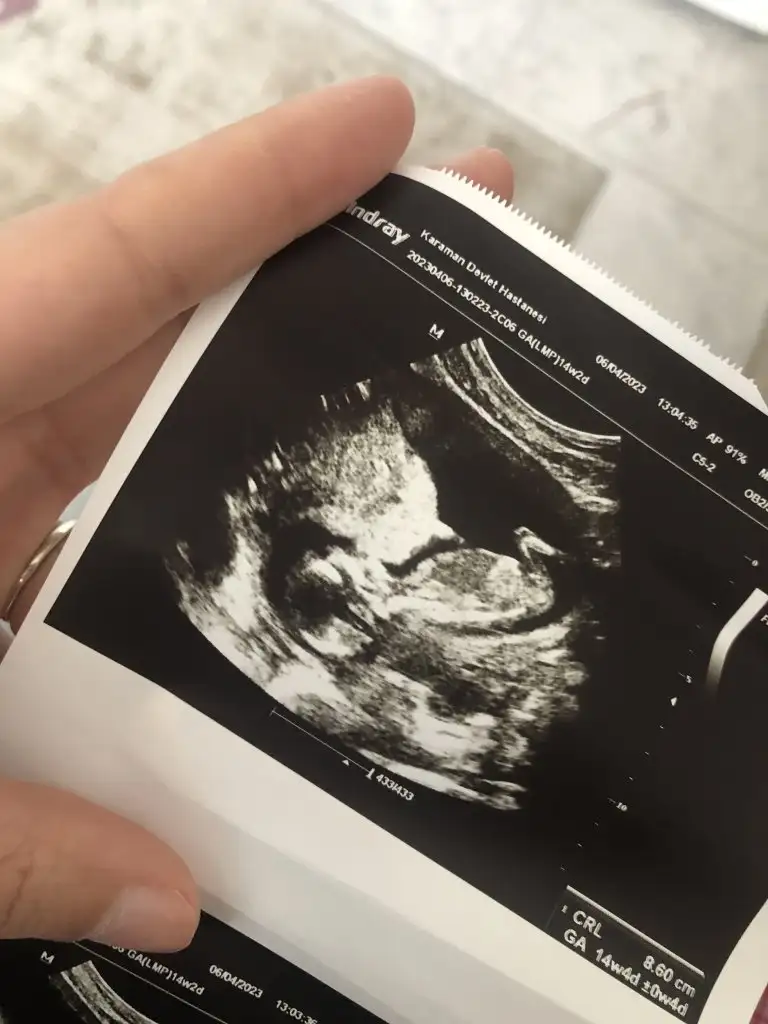

Inslh canim cok sagol yinede amin inslhCanım ben cinsiyetten çok anlamıyorum öncelikle bebeğin sağlıkla geldin içimden kız geçti o yüzden

doktor da bulunmustur diye dusunuyorum. tatli bi kiziniz olacak allah bağışlasın.Bana da tahminlerde bulunur musunuz 11+6 yız

Bu kız ya. Bacak arasındaki çizgi yatay ve iki çizgi görünüyor. Net olmadığı için 3 çizgi görünmemişBana da tahminlerde bulunur musunuz 11+6 yız

Doktor da kız dedi evetBu kız ya. Bacak arasındaki çizgi yatay ve iki çizgi görünüyor. Net olmadığı için 3 çizgi görünmemiş